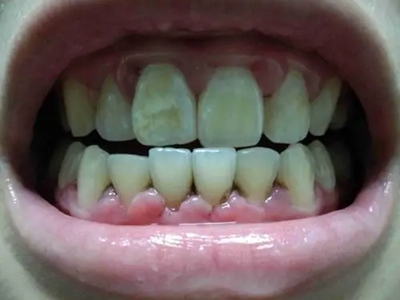

牙釉质发育不全牙齿白斑图

牙釉质发育不全患者可以仅仅出现牙齿色泽和透明度的改变,形成白垩色釉质,即类似于牙齿上有白斑,此时牙冠形态通常较完整。